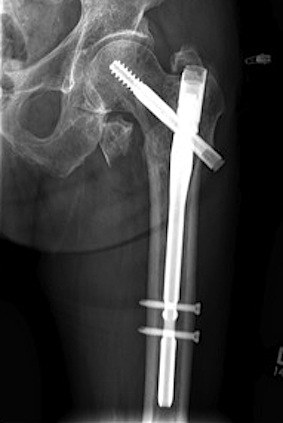

Sliding hip screw/dynamic hip screw

Cephalomdeullary nail

- Short / long

- one screw / two screws / blade

Cephalomedullary nail / Proximal femoral nail

Mechanical advantages

- load sharing rather than load bearing

- decreases lever arm

- supports medial cortex

Surgical advantages

- smaller incision / minimally invasive

- reduced blood loss

- shorter surgical times

Indications

- reverse oblique

- unstable fracture / loss of lateral buttress / loss posteromedial support

- subtrochanteric extension